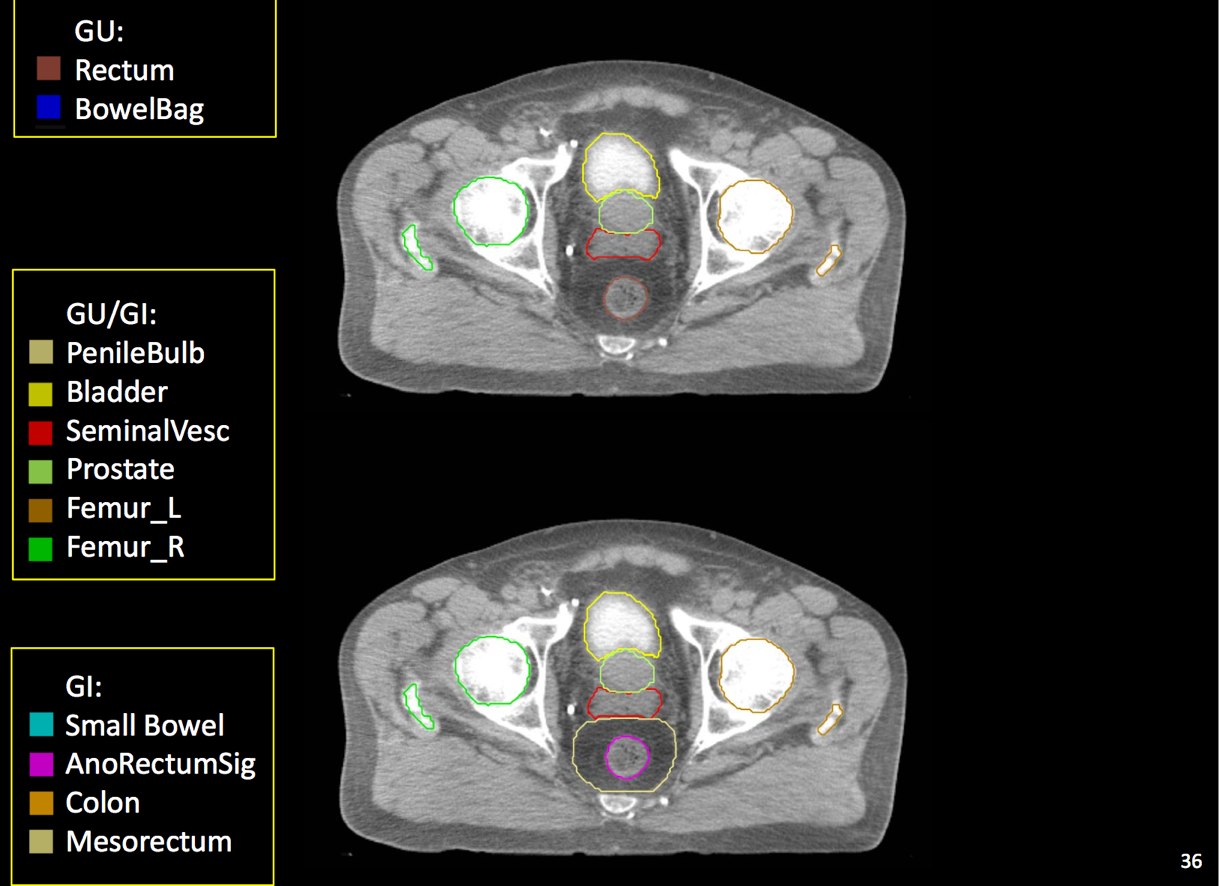

At a minimum, the following contours should be available to the planners:

• prostate

• seminal vesicles (treat at least proximal if risk calculated > 15% --ucsf)

• pelvic lymphatics (if treatment indicated -- risk > 15% -- ucsf)

• femoral heads

• rectum

• bladder

• bowel (where necessary due to bowel prolapsing below the bladder)

• penile bulb

The target volume (CTV) is defined as the prostate and seminal vesicles. The planning target volume expands the CTV to take into account setup uncertainties, both systematic and physiologic. By using daily image guidance, where available, physiologic parameters are more controlled and allow the reduction of CTV expansion required to fully cover the prostate and adjacent tissue at risk.

There is significant variation of contours and techniques. The apex and base are regions most susceptable to variation. 3D perspectives help signficantly reduce this variation using transverse, sagital and coronal projections to determine the true extent of the prostate. More recently contouring atlases have been developed by the RTOG with grant assistance from the NCI and are available here. The following images are obtained from the RTOG contour atlases as an excerpt demonstrating areas of potential uncertainty.

GTV is the entire prostate. If a urethrogram is used, the apex is designated at the visualized prostate or 5 mm superior to the tip of the urethrogram dye. The initial field encompasses the pelvic lymphatics from L4/L5, pre-sacral nodes from L5-S1 and inferiorly below the prostate by 5 mm. The internal and external iliac nodes should be covered below the SI joints. Lateral fields should include the posterior extension of the seminal vesicles. The usual posterior border is S2/S3, but this may vary based on CT imaging and imaging should take precedence. The inferior extent of the internal iliacs are the tops of the femoral heads, the inferior extent of the obturator nodes is the top of the pubic symphysis.

CTV construction is a selective expansion on the prostate GTV. For the lymphatic portion of treatment, the CTV should be a 7 mm expansion around the contoured vessels, corrected for anatomical barriers. The nodal CTV expansion should not extend outside of the true pelvis, into muscle, bone or organs such as bladder, rectum and bowel. Treatment will be to the PTV planning target volume which will consist of a minimum of 0.5 cm expansion on the CTV and a maximum expansion of 1.5 cm in all dimensions.

There are recent efforts to standardize segmentation names for radiotherapy treatment planning. This is encouraged to allow for inter-institution comparisons, particularly on protocol patients, but it may also assist institutions in comparing dosimetry should additional radiotherapy or other dose questions arise. The normal clinical structures to be identified are: